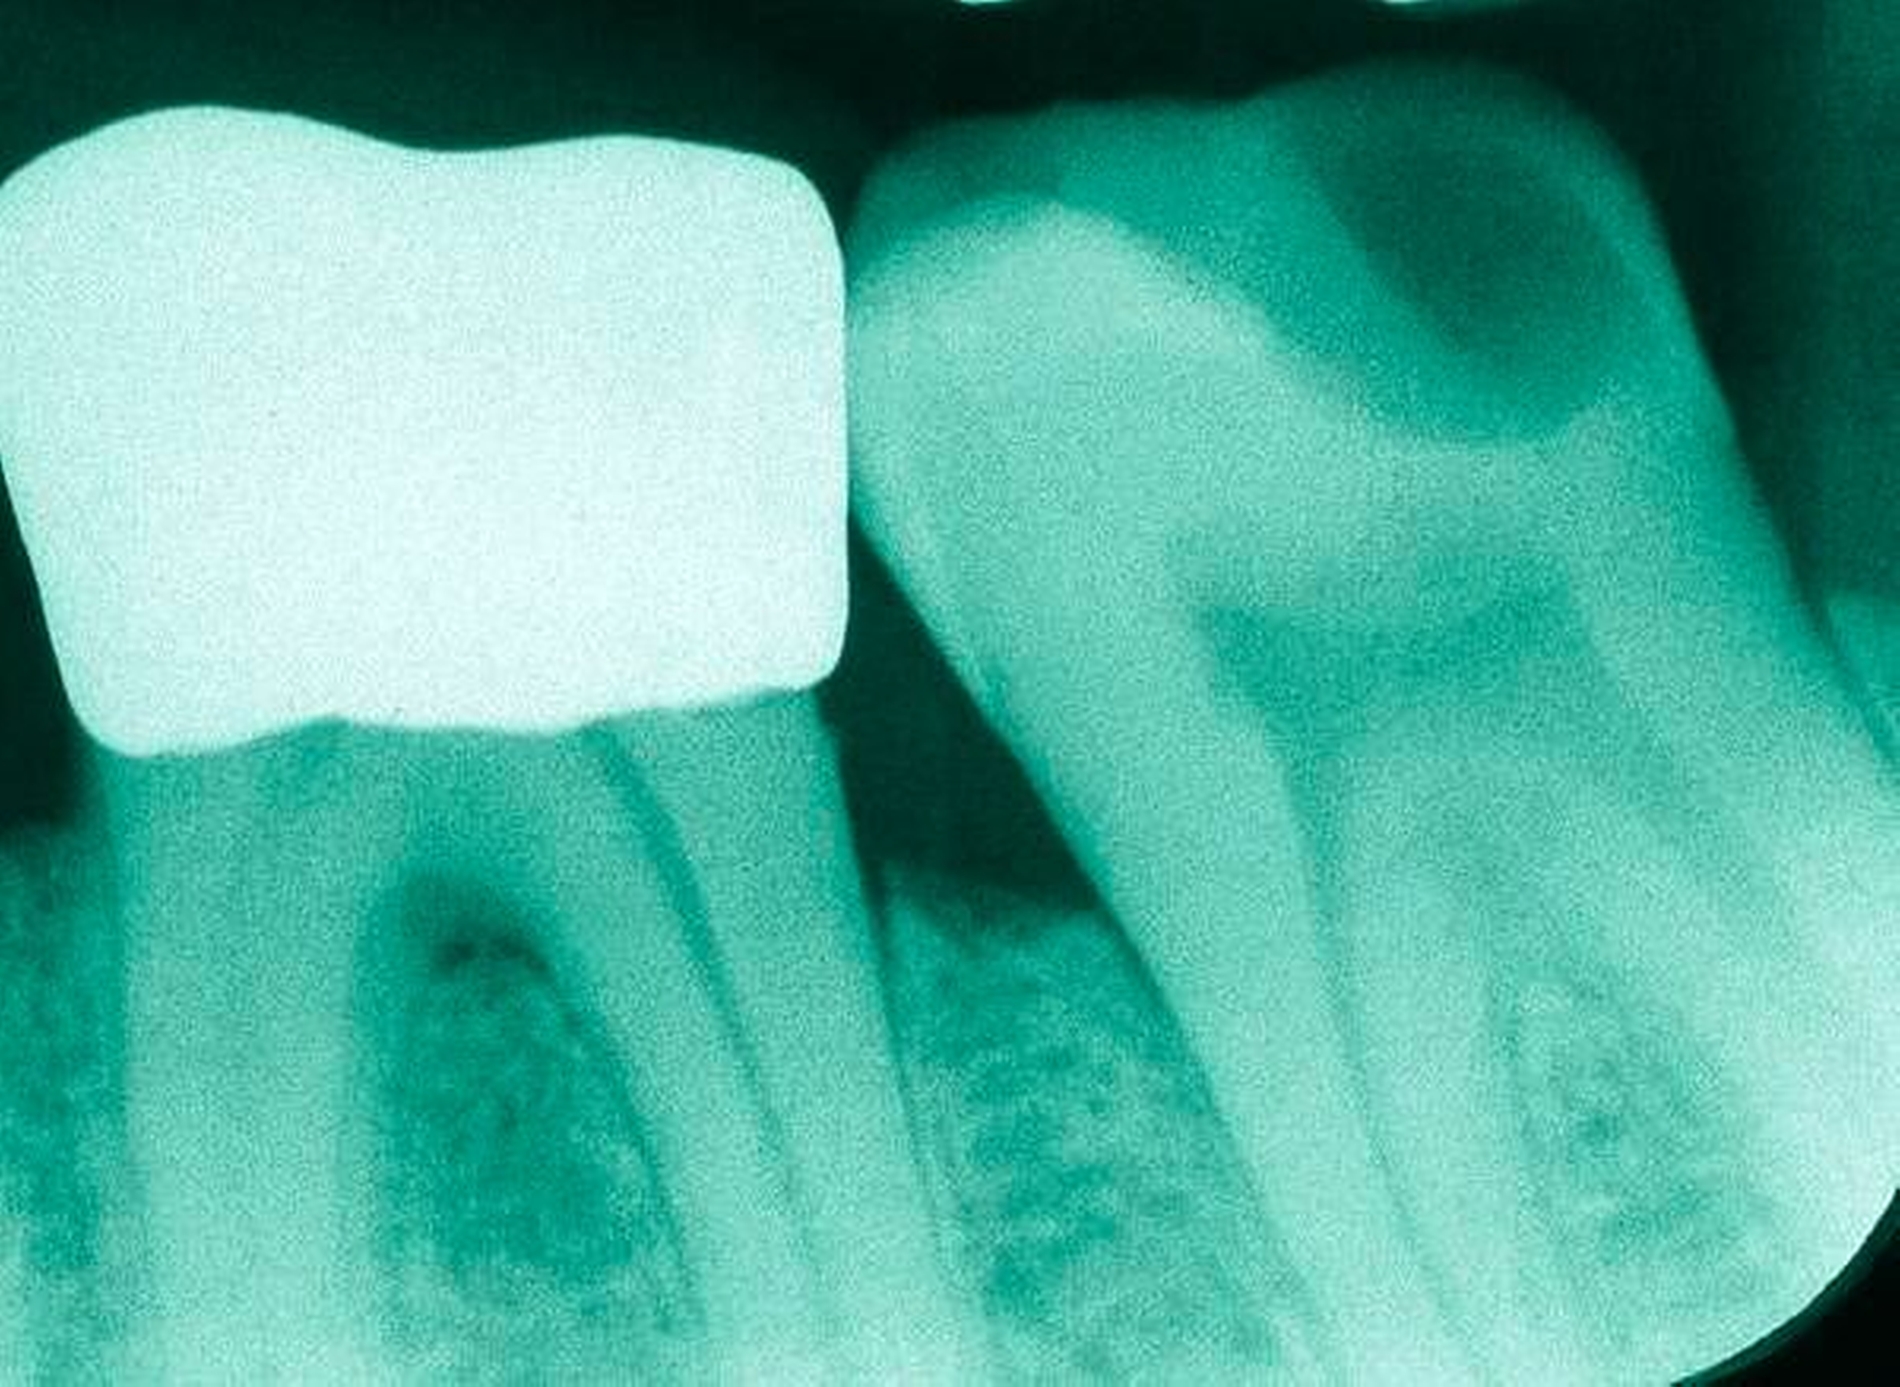

Abbildung 3: ausgedehnte Kronen- und Wurzelkaries unter einer Krone am Pfeilerzahn 47 einer seit Jahrzehnten eingegliederten Brücke von 45–47 bei einer 71-jährigen Patientin, die nach einer zerebrovaskulären Erkrankung unter Antikoagulantientherapie steht, vor etwa zwei Jahren hat sie eine Umstellung auf eine fluoridfreie Zahnpaste vorgenommen.

3. Restaurative Versorgungen bei Wurzelkaries

Freiliegende Wurzeloberflächen können im Alter ein locus minoris resistentiae für Karies sein. Im Zusammenspiel ungünstiger Ernährungsgewohnheiten, nachlassender Mundhygiene sowie Änderungen von Speichelquantität und -qualität kommt es zuweilen zu einem präventiv und restaurativ schwer beherrschbaren Auftreten von Wurzelkaries. Gut zugängliche Kariesläsionen können mit einphasig eingebrachtem Komposit (R1-Restaurationen) angegangen werden (Abbildungen 3 bis 5). Bei schwerer zugänglichen Arealen kommt ein zweiphasiges Vorgehen in Betracht (R2-Restaurationen). Das Vorgehen bei der R1- und bei der R2-Technik wurde mehrfach beschrieben [Frese et al., 2014a, b, c, d; Staehle et al., 2014, 2017]. Im Fall von zirkulärer Wurzelkaries sollte frühzeitig eingegriffen werden, da ansonsten die gesamte Zahnkrone frakturieren kann.